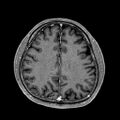

2. 2023/11/21 밤, 뇌 MRI 촬영

1. 폐암이 유독 전이가 활발한 이유는 폐에 연결된 동맥이 심장을 통해 전신으로 퍼지기 때문이다.

2. 비소세포폐암은 국소 재발보다는 뇌, 뼈, 간 등에 전이 되는데, 특히 뇌전이가 자주 발생된다. 이를 확인하기 위해 뇌 MRI를 찍었다.

3. MRI는 강한 자기장을 사용한다. 금속물질을 있는지 체크한다. 검사시 소음이 심하다. 안전 공구의 한 종류인 귀마개를 제공한다.

3. 뇌전이는 없다고 함.